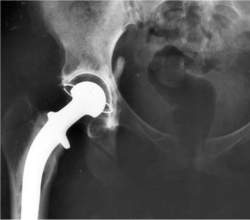

Implantes para quadris e joelhos

Implantes de metal sobre metal

Esses implantes são classificados pela FDA como dispositivos de alto risco. No entanto, tem sido permitido que eles entrem no mercado sem testes clínicos.

Esses implantes apresentam falhas em uma taxa perigosamente alta, exigindo cirurgias reparadoras pelo menos quatro vezes mais frequentemente do que no caso da cirurgia tradicional.